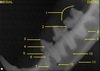

Left mandibular premolars and molar

Left mandibular premolars and molar